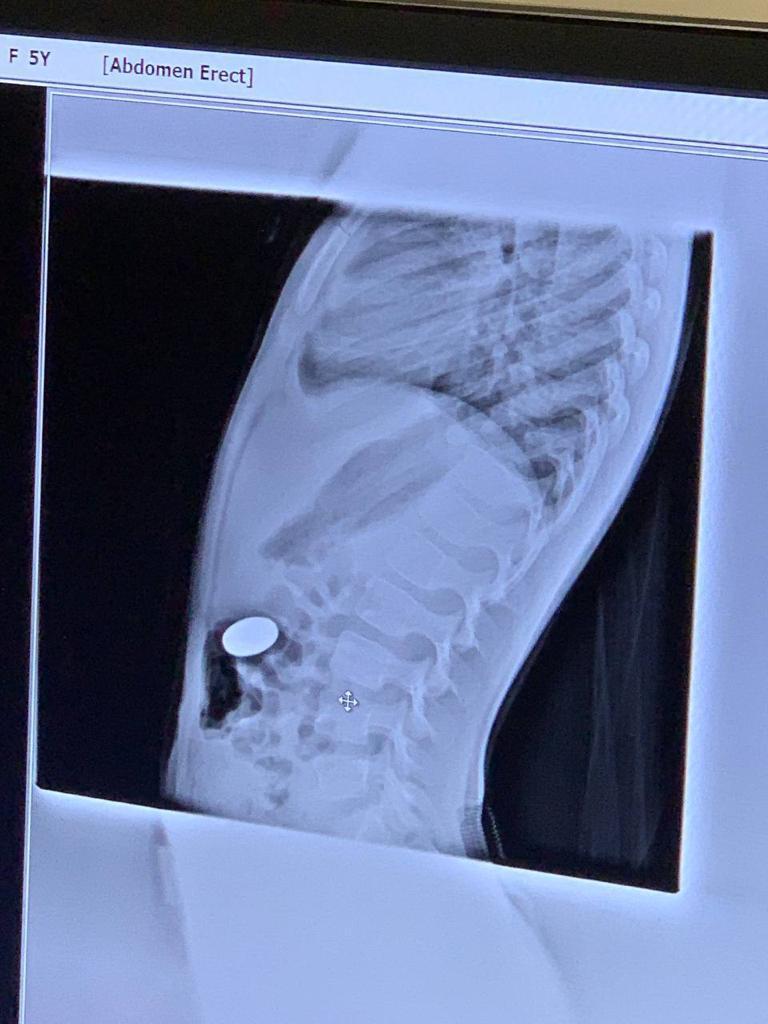

Через 20 минут после операции, в приемное отделение залетают ошарашеные родители с чадом около 4-5 лет. Монету проглотила.

Делаем Рентген

*скрепка не внутри, она для ориентации*

Я хмуро посмотрел на рентгенолога. Рентгенолог посмотрел на снимки, а потом на меня (искра, буря, безумие) - В поперечно-ободочной. Сама выйдет. - заключил он.

Посмотрели. 5ти Рублевая монета в желудке. Достали без происшествий. Отпустили с богом.